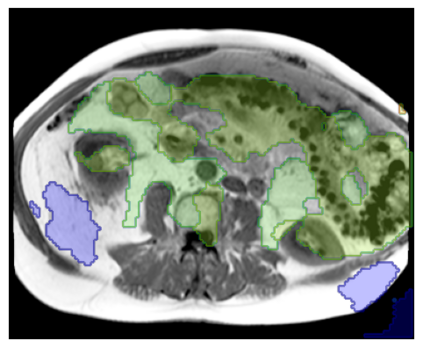

Purpose: To introduce a deep learning model capable of multi-organ segmentation in MRI scans, offering a solution to the current limitations in MRI analysis due to challenges in resolution, standardized intensity values, and variability in sequences. Materials and Methods: he model was trained on 1,200 manually annotated MRI scans from the UK Biobank, 221 in-house MRI scans and 1228 CT scans, leveraging cross-modality transfer learning from CT segmentation models. A human-in-the-loop annotation workflow was employed to efficiently create high-quality segmentations. The model's performance was evaluated on NAKO and the AMOS22 dataset containing 600 and 60 MRI examinations. Dice Similarity Coefficient (DSC) and Hausdorff Distance (HD) was used to assess segmentation accuracy. The model will be open sourced. Results: The model showcased high accuracy in segmenting well-defined organs, achieving Dice Similarity Coefficient (DSC) scores of 0.97 for the right and left lungs, and 0.95 for the heart. It also demonstrated robustness in organs like the liver (DSC: 0.96) and kidneys (DSC: 0.95 left, 0.95 right), which present more variability. However, segmentation of smaller and complex structures such as the portal and splenic veins (DSC: 0.54) and adrenal glands (DSC: 0.65 left, 0.61 right) revealed the need for further model optimization. Conclusion: The proposed model is a robust, tool for accurate segmentation of 40 anatomical structures in MRI and CT images. By leveraging cross-modality learning and interactive annotation, the model achieves strong performance and generalizability across diverse datasets, making it a valuable resource for researchers and clinicians. It is open source and can be downloaded from https://github.com/hhaentze/MRSegmentator.